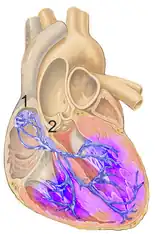

Causes include heart damage, such as a heart attack or myocarditis, increased right ventricular pressure, such as with pulmonary embolism or cor pulmonale, and rarely high blood potassium.[1] Though some cases occurs without any specific cause.[2] The underlying mechanism involves damage to the right bundle branch.[1]